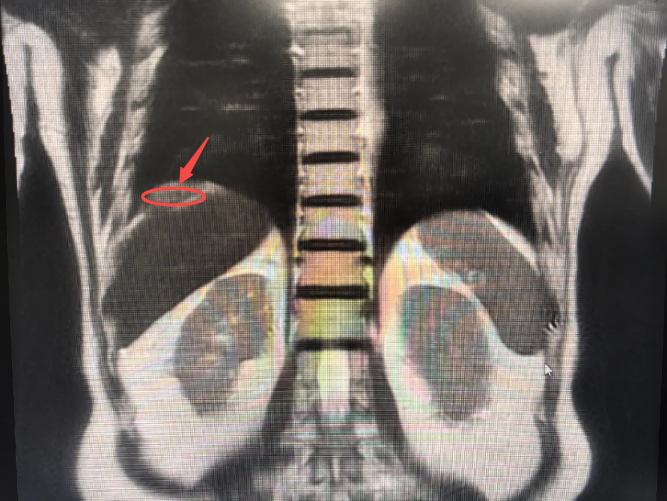

近期,李爷爷在体检中发现肿瘤标志物CEA升高,经全身PET/CT检查,发现其右膈下腹膜有一处新发病灶,糖代谢活性增高(提示肿瘤可能性大),且与肝右后叶包膜分界不清,临床考虑为腹膜转移性病变。

在游离肝周粘连后,团队不仅找到了预定的目标——那个约5cm*4cm的膈肌表面腹膜下的“炸弹”(术前发现的新病灶),还意外在肝脏上发现一个0.5cm的“小地雷”(术前没发现的微小病灶)。经现场讨论,团队决定将两个病灶一并切除。